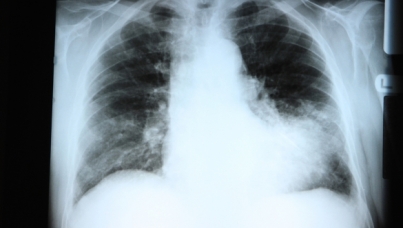

Les Européens peu conscients des risques que représente la pneumonie

L’étude PneuVUE*, réalisée par l’équipe Santé d’Ipsos pour le laboratoire Pfizer met en lumière le manque de connaissances des Européens concernant les moyens de prévention existant pour lutter contre la pneumonie et pointe le relatif désintérêt de la population vis-à-vis des risques que représente cette maladie. Le rôle de sensibilisation des professionnels de santé s’avère donc crucial pour favoriser un vieillissement en bonne santé des populations.